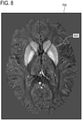

• the resulting susceptibility map is used to refine the segmentation to improve the initial segmentation, see Fig. 7 below, to better describe tissue boundaries in the susceptibility, see Fig. 8 below.

• Figs. 7 and 8 show an example of a QSM image 700.

• the QSM image 700 is shown with eight segmentations.

• the segmentations shown in Fig. 7 are from an initial segmentation for example from a survey image. Upon examining Fig. 7 it can be seen that the segmentations do not line up with all of the structures shown in the QSM image 700 very well.

• Fig. 8 the segmentation has been performed on the QSM image 700 using an image segmentation module that has been modified to find the structures in the QSM image 700. It can be seen that the segmentation is much more accurate and better fits the anatomy of the subject shown in image 700.

• the segmentations shown in Fig. 8 may be an example of a first segmentation of the QSM image.

• the segmentations 800 may be used for further reconstruction of the QSM image again.